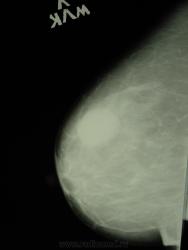

в 2008 году у данной пациентки была выявлена киста левой млочной железы, на УЗИ- гипоэхогенное образование. Не лечилась, не пунктировали. Менопауза 8 лет. На новых маммограммах кисты нет, куда же она делась????

в левой молочной железе обьемное образование может быть кистой с густым вязким содержимым что и показывает узи как гипоэогенное, но аваскулярное? нужна пункция

на узи была поставлна киста, и у онколога с кистой наблюдалась, пункции не было.  разместила этот случай, потому что я с такой динамикой не сталкивалась, и хотелось узнать может у кого были подобные случаи))))))

В первом случае складывается впечатление всё таки о кисте. В эту пользу может говорить и её инволюция. Хотя весьма странно что не сделаны прицельные снимки...

По первому случаю: кисты могут очень быстро появляться и так же быстро исчезать или уменьшаться в размерах, возможно самостоятельное дренирование кист через млечные ходы. С 2008 г отмечается значительное уменьшеньшение размеров кисты, появление не четкого контура, участков тяжистости за счет склерозирования. Сейчас надо отправить пациентку на УЗИ (посмотреть размер образования, который мы четко ценить не можем, внутренний контур, содержимое, возможно пункция). Иногда встречается и рак в кисте.